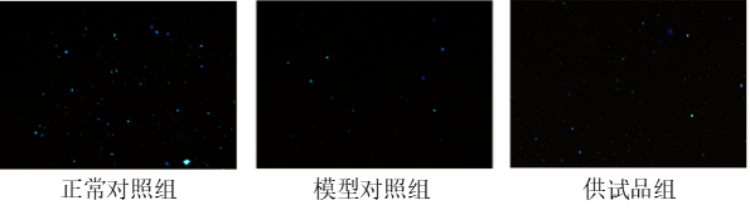

服用一段时间供试品后,我们收集斑马鱼样本,采集精巢组织,利用精子活力荧光染色试剂盒进行精子染色(呈蓝色),在荧光显微镜下观察精子数量的变化。

图1. 斑马鱼精子数量表型图

(蓝色颗粒为精子)

从实验结果可以看到。模型对照组的精子数量较正常对照组明显减少,供试品组相对模型对照组精子数量明显增多。